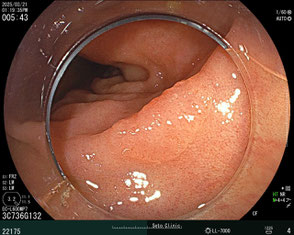

ポリープ治療の事例

強調画像で詳細に観察して治療することに決定